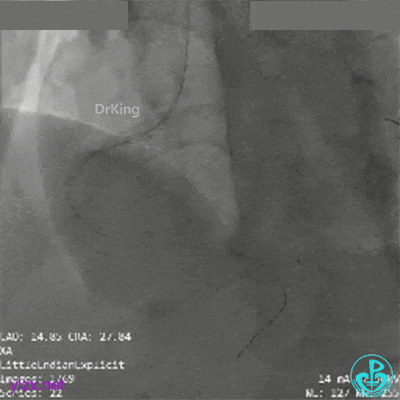

近端3.5×33mm支架至开口,中段接3.0×33mm支架。后扩张处理后远端仍然造影剂滞留。

PL近端2.5mm切割球囊扩张后,造影剂滞留改善。

远端至PL近端接2.75×33mm支架后,血流彻底恢复。

3.0×15mm及3.5×15mm球囊优化以后最后造影。